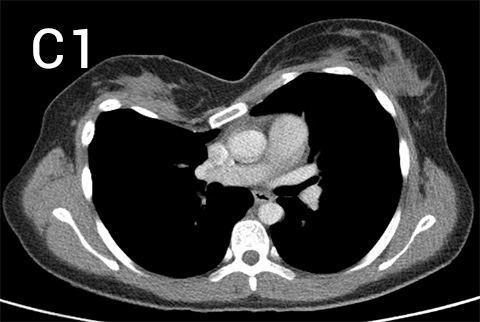

Pre-operative photos (A and B) with chest CT (C, multiple slices of upper (1), middle (2) and lower (3) chest) showing a long very asymmetrical pectus excavatum deformity in a 35 year old patient with striking symptoms of constrictive feeling in her chest